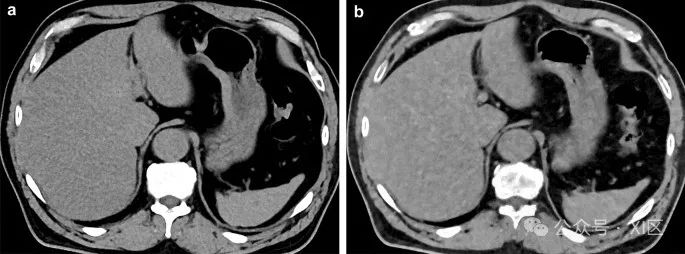

图1 光子计数CT(A)和传统双源CT(单能量模式)(B)在不同日期扫描的胆总管结石患者的腹部CT平扫图像。尽管光子计数CT的辐射剂量(CTDIvol:7.5 mGy)低于传统CT(11.9 mGy),但光子计数CT的图像噪声显然低于传统CT。胆总管中的分层钙化结石(箭头)在光子计数CT中显示得更加精细。

图2 光子计数CT(A,C)和传统双源CT(单能量模式)(B,D)在不同日期扫描的动脉期(A,B)和平衡期(C,D)的肝脏增强动态CT图像。肝右叶可见小血管瘤(箭头)。尽管光子计数CT的辐射剂量(CTDIvol:4.6 mGy)恰好是传统CT(9.2 mGy)的一半,图像质量仍保持可比性。光子计数CT在成像体型较大的患者时也具有优势。传统探测器CT对肥胖患者进行双能量成像时,由于低kVp采集缺乏光子,总体图像质量下降。Hagen等人报告称,在肥胖患者中使用光子计数CT进行增强腹部CT与常规单能量CT相比,图像质量相似或提高,并且显著减少了辐射剂量。